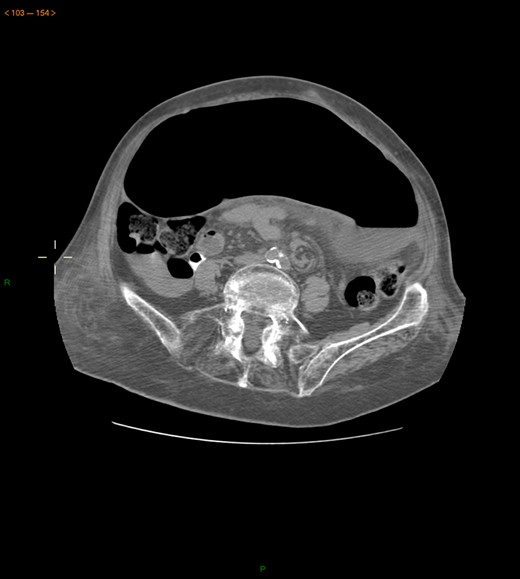

Case 1: A 40-year-old men, without previous abdominal surgery or history of abdominal trauma or peritoneal infections was admitted to the emergency department with generalized abdominal pain, nausea and vomiting. Physical exam revealed a distended abdomen, with pain in the epigastrium without tenderness. Laboratory investigation on admission was normal. Abdominal X-ray revealed a marked sigmoid colon distension suggestive of a colonic volvulus. A colonoscopy was conducted and revealed necrosis of the colon sigmoid apparently form a colonic volvulus. Abdominal-pelvic computerized tomography(CT) was conducted and a colonic volvulus associated with a transmesocolic hernia with transmural necrosis of the colon sigmoid was identified (Fig. 1). The patient was proposed to laparotomy during which a volvulus of sigmoid colon with transmural necrosis in a strangulated descendent transmesocolic hernia was identified. A Hartmann procedure was conducted and the patient was discharged at sixth post-operative day. At 2 year follow-up consultation, the patient remained free of complains, with the intestinal transit re-established.

Abdominal-pelvic CT—coronal plane: colonic volvulus associated with a transmesocolic hernia with transmural necrosis of the colon sigmoid.